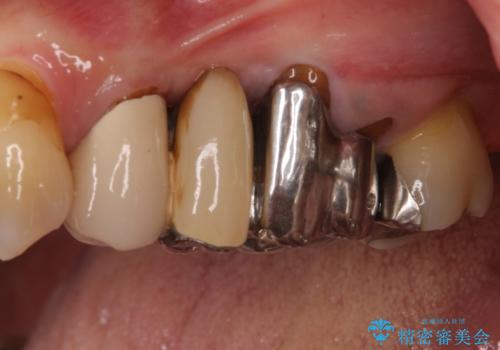

- 奥歯のブリッジにものが挟まるとのことで来院された患者様です。

奥歯の3本の歯根のうち1本は保存困難な状況であったため、1本を抜根し、傷の治癒を待った後にオールセラミックブリッジにて補綴することとしました。

ものが挟まる原因は、保存困難なほど歯肉から露出していた歯根にあったため、抜根することで気になっていた問題は解消されました。